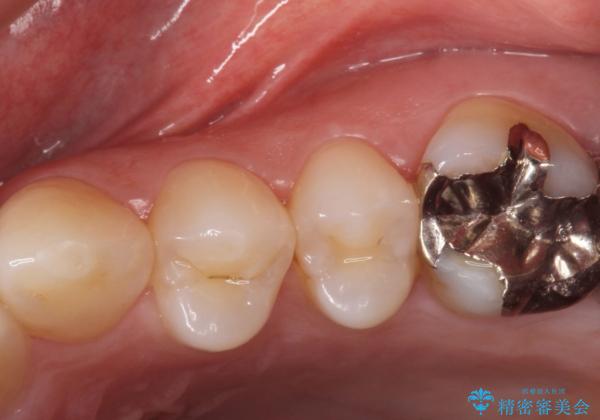

銀の詰め物を拡大鏡下で取り除き、う蝕がないことを確認してから

ZrCrの被せ物で治療を行いました。

銀の詰め物の範囲が大きいほど

やりかえをする時、セラミックの詰め物だと割れるリスクがあるため

ZrCrの被せ物のご案内をする事があります。